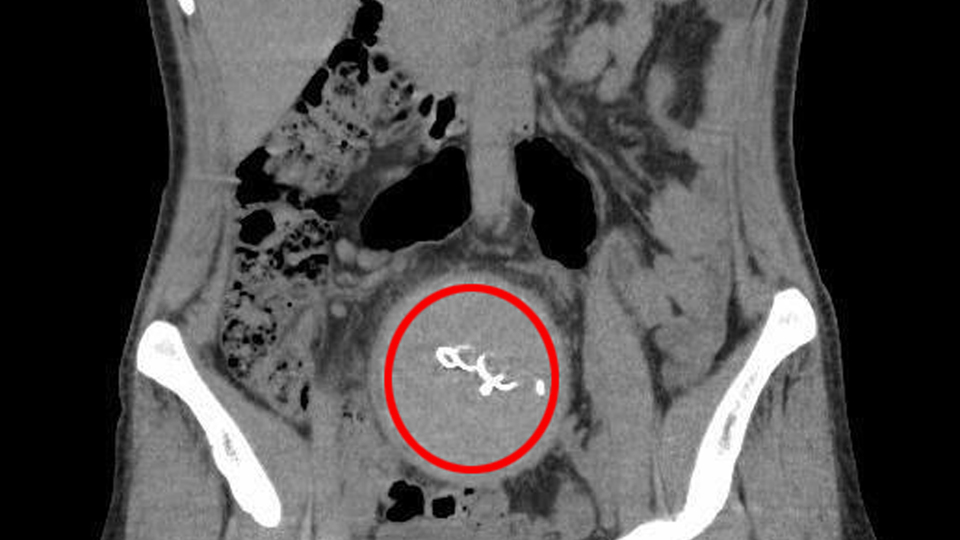

Burada yapılan kontrolde doktor acil tomografi çektirmesini istedi. Çekilen tomografide Y.S.´nin vücudunda doğum sonrası unutulan sargı bezi görüldü. Büyük şok yaşayan Y.S., 2 yıldır yaşadığı ağrılara ihmalin sebep olduğunu öğrendi. Y.S.'nin karnında unutulan yaklaşık 30 santimetre uzunluğundaki gazlı bez ameliyatla çıkarıldı. Y.S., hastane ve doktor hakkında hukuki süreci başlatması için avukatı Hasret Baş´a başvurdu.